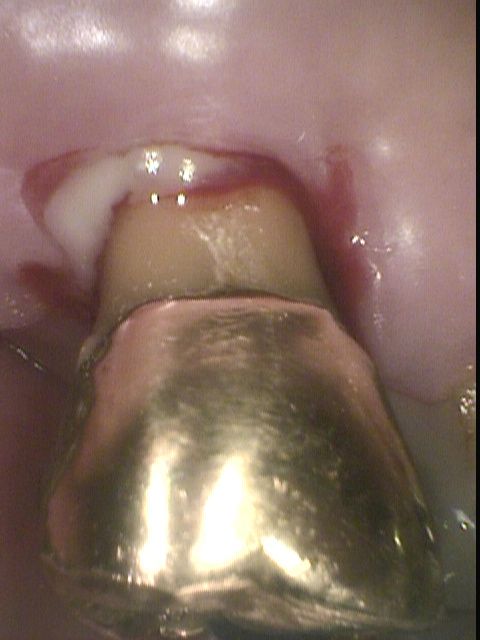

Photo-1

【歯周病も重症になるとブラッシングだけでは、このように出血の改善はみられず、細菌の制御(殺滅・除去)とレーザー治療が必要

上記、重症の歯周病のポケットから採取された大量のrodやT.d菌。